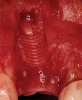

Figure 14  (Case 2) Failed implant at surgical exposure.

Figure 15  (Case 2) Defect after implant removal.